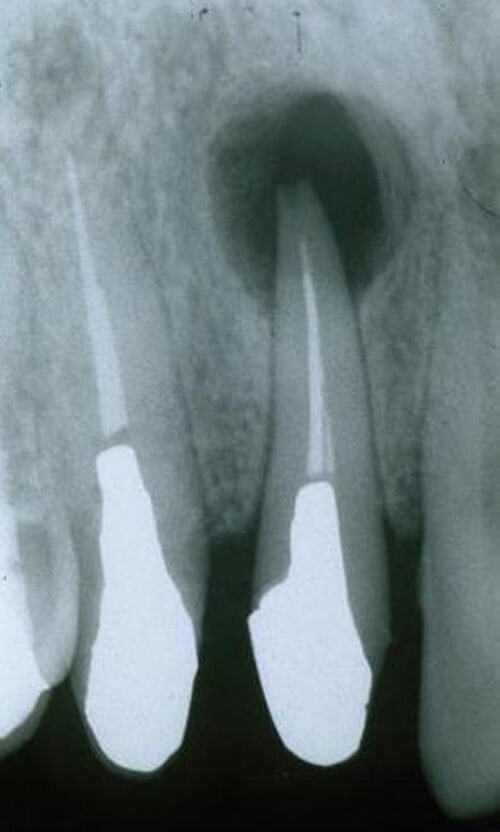

<歯根端切除術+嚢胞摘出術>

嚢胞と原因の歯の根の一部を一緒に摘出します。

※術後のレントゲンで嚢胞を摘出した部位に骨の形成を認めます。